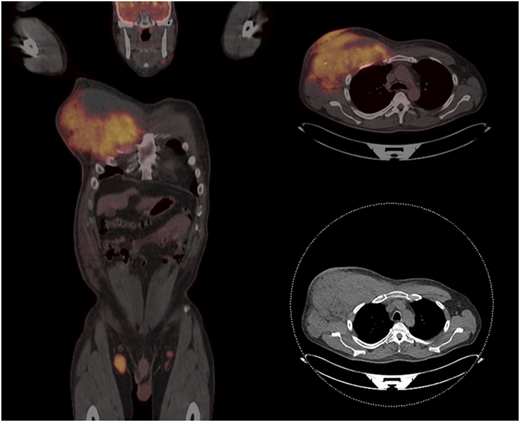

Patient 2 was a 61-year-old man who had presented with a right neck mass 8 years ago. A biopsy showed FL grade 1. He had undergone active observation until several months ago, when he noted right axillary swelling. He was evaluated in the clinic and was found to have an extensive mass in his right axilla and infiltrating the chest wall (Figure 2). A biopsy showed transformation to an aggressive lymphoma with a Ki67 of 95% and sheets of mitotically active intermediate to large cells with a high nucleus/cytoplasm ratio, CD20+CD10+MYC+BCL2+. Subsequent fluorescence in situ hybridization confirmed rearrangements of MYC and BCL2.

Figure 2.

Patient with FL transforming to HGBL-DHL/THL, showing massive infiltration of the right chest wall and axillary adenopathy.